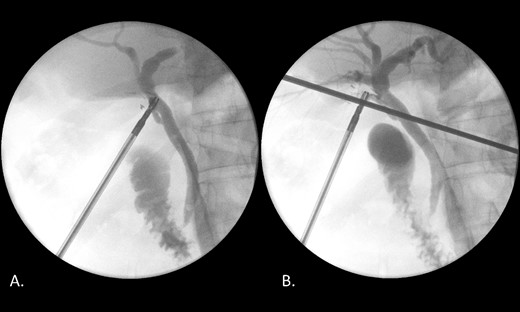

Laparoscopic cholecystectomy, IOC and transcystic bile duct exploration (TCBDE) were performed two days later. Intraoperatively, the gallbladder did not appear inflamed however there were signs of chronic inflammation with fibrosis within the hepatocystic triangle. An IOC demonstrated a distal CBD filling defect with flow into the duodenum suggesting persistent partial obstruction (Fig. 4). A TCBDE was performed with extraction of soft chalky sludge from the cystic duct. A completion IOC demonstrated no ongoing filling defect with flow to the duodenum and intrahepatic ducts. Histopathological sections of the gallbladder demonstrated findings compatible with chronic cholecystitis without evidence of dysplasia or malignancy.

(A) IOC demonstrating a distal filling defect in the CBD causing partial occlusion. (B) IOC following TCBDE demonstrating no remaining filling defect with tapering of the distal CBD with contrast flow to the duodenum.